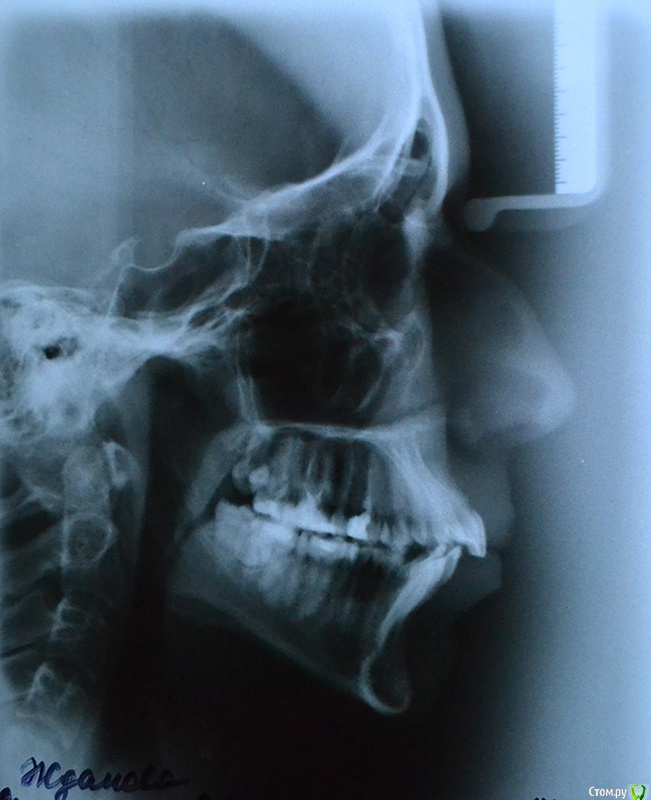

Мне 22 года, планирую исправить проблемы с прикусом, сейчас ищу информацию, рассматриваю варианты.

Очень нужен совет - действительно ли в моем случае лучшим выбором будет удаление 4ок на обеих челюстях?

Консультировалась у двух ортодонтов, оба сказали: без вариантов, зубы крупные, места не хватает.

Второй врач пугал, что если и возможно не удалять и как-нибудь "натянуть" зубы в более-менее правильное положение, то все равно стоит только снять брекеты, как прикус тут же вернется в исходное состояние и вообще будет повышенная нагрузка на челюсти.

А я никак не могу решиться. Особенно почитав этот форум, где у многих людей после удаления возникают проблемы с эстетикой лица и суставами. Кроме того, я боюсь, что без четверок на ВЧ зубы провалятся слишком далеко назад. Да, передние резцы сравняются с остальными, но мне бы не хотелось, чтобы все челюсти в общем, а за ними и губы сильно сдвинулись "вглубь", это еще больше испортит лицо.

В общем, прилагаю фото, подскажите, пожалуйста, что можно с этим сделать.

П.С. Само собой, я буду удалять лежащий на боку зуб мудрости) И правую нижнюю 8ку, скорее всего, тоже.